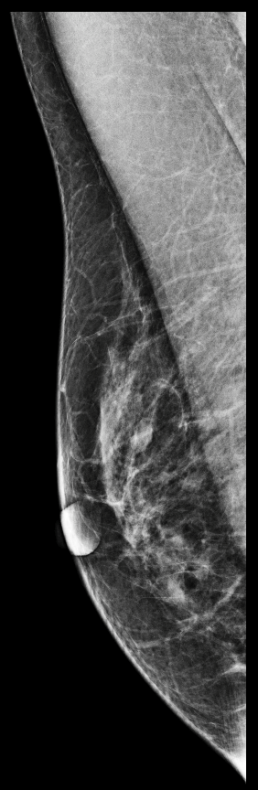

During the screening, two masses were found, one on the right breast (2cm DTN) and the other on the left breast (A1 cm DTN), categorized as suspicious.

The patient was called back for an ultrasound. The following biopsy performed showed lobular cancer infiltrating the left breast (two masses).

MammoScreen indicates one of the suspicious masses on the left breast in score 8 on tomosynthesis.